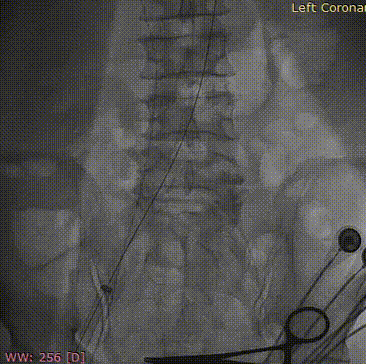

球囊扩张

瓣膜初始定位

瓣膜共3次释放

随着宋光远教授的口令“起搏、扩张、造影、抽瘪、停起搏”,刘新民、姚晶医生密切配合迅速完成球囊扩张,球囊扩张后患者血压立即升至100/60mmHg。随着球囊导管的撤出,刚刚组装好的瓣膜随即送入患者体内。宋光远教授与刘新民、姚晶、苑飞医生密切配合,逐步释放瓣膜,最终瓣膜完美释放,位置理想。